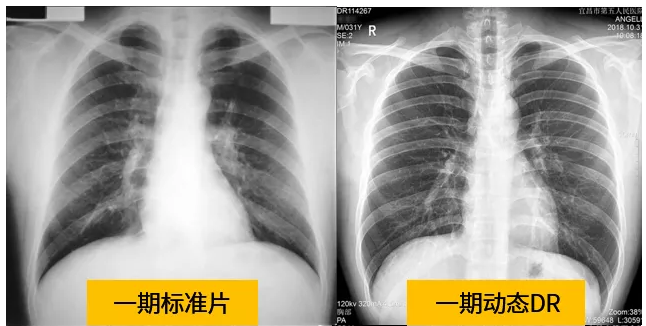

動(dòng)態(tài)dr的拍攝效果圖

動(dòng)態(tài)DR技術(shù)與普通DR單截面診斷的不同就是在操作過(guò)程中,可以隨時(shí)切換成透視模式,透視/攝片模式實(shí)時(shí)切換,對(duì)陰影進(jìn)行多角度動(dòng)態(tài)的鑒別。實(shí)時(shí)點(diǎn)片、實(shí)時(shí)回放、連續(xù)點(diǎn)片等多功能大大的增加了初診的準(zhǔn)確率。在小陰影的形態(tài)和性質(zhì),特別是不規(guī)則小陰影的判斷方面提升,從而達(dá)到提高胸片整體判斷準(zhǔn)確性。

根據(jù)數(shù)據(jù)統(tǒng)計(jì)表現(xiàn),利用動(dòng)態(tài)dr進(jìn)行檢查的話,圖像的質(zhì)量和輻射劑量相對(duì)較少。并且動(dòng)態(tài)DR在圖像清晰度和射線穿透力方面完全能達(dá)到塵肺診斷的要求。這種檢查效果的精準(zhǔn)和便捷性是和普通設(shè)備不一樣的,動(dòng)態(tài)DR塵肺攝影應(yīng)用于塵肺疾病診斷中,可以提高檢出率及優(yōu)片率。